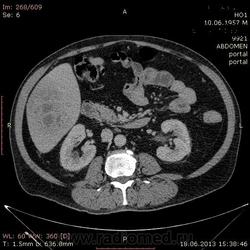

На абсцесс похоже

+1. Контраст вводили?

На мой взгляд, абсцесс.

Тоже за абсцесс.

Cпасибо , коллеги.Сегодня больного прооперировали диагноз абсцесс правой доли печени.Оказывается больной когда - то получил тупую травму живота, об этом нам не говорил.....